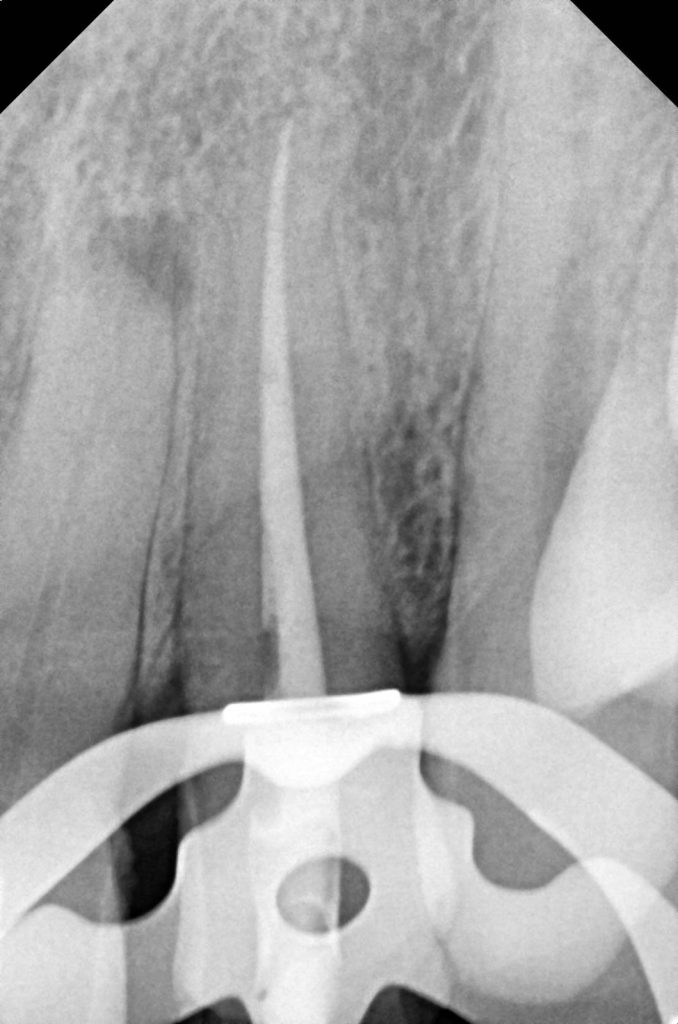

- Prior root canal therapy with open apex—managed using MTA-based apexification.

- Post-traumatic discoloration due to pulpal necrosis.

- Residual esthetic defect after apexification.

Previous MTA apexification provided apical stability, allowing safe buildup and crown retention. Non-vital bleaching minimized aggressive preparation and preserved tooth structure.